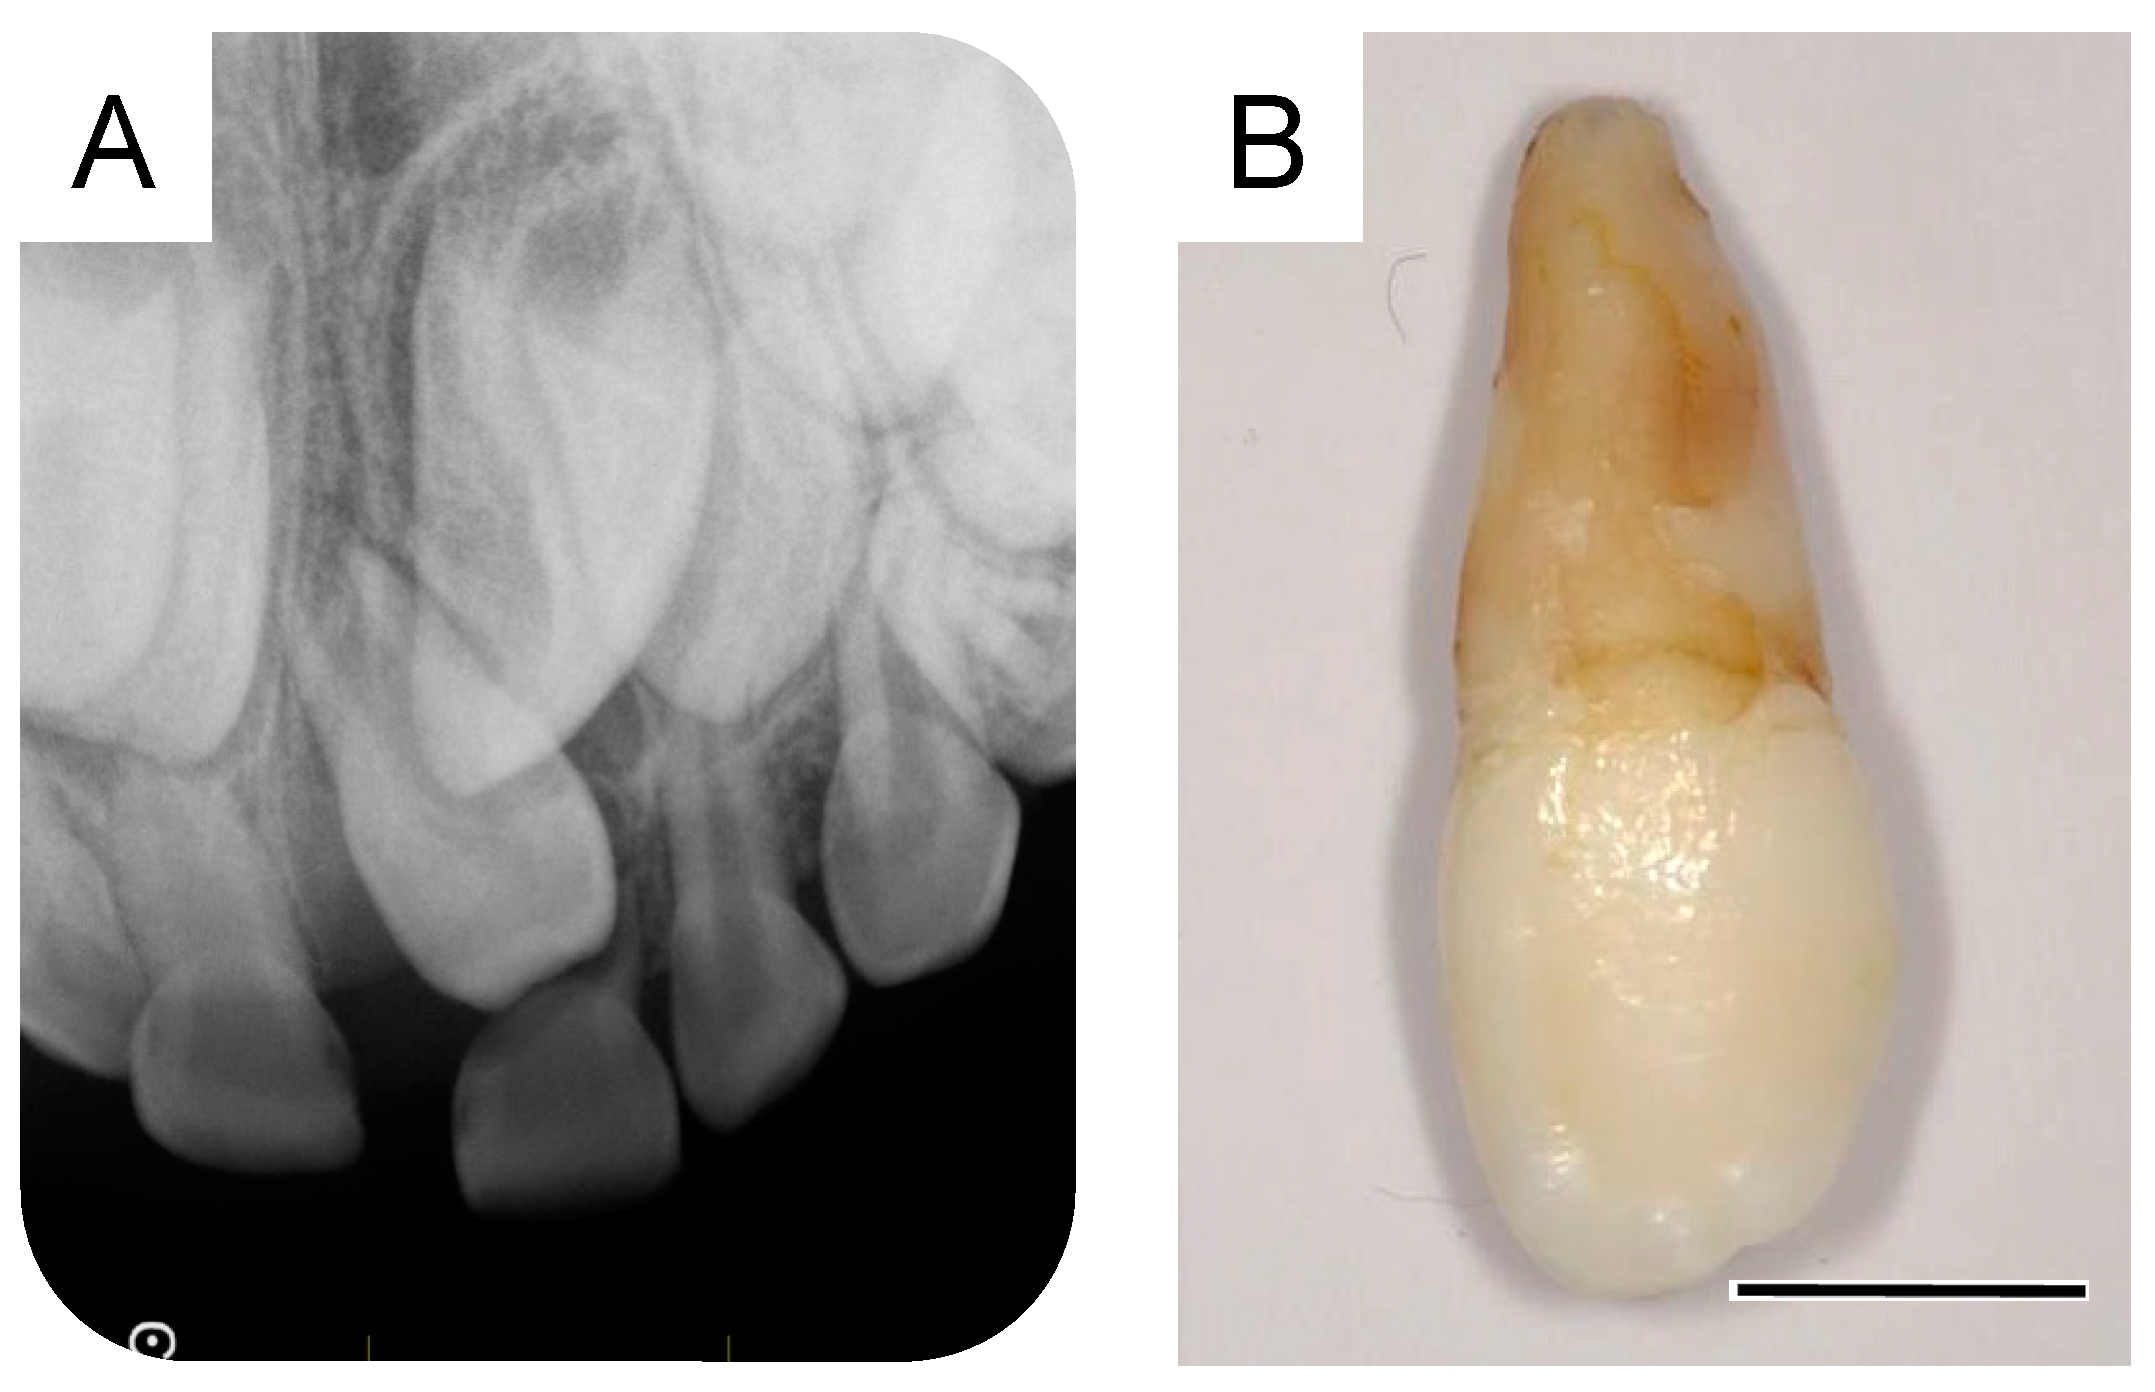

A small radiolucency was observed near the crown of the maxillary left central incisor in the dental X-ray image taken during the first extraction. The dental X-ray images at 6 years and 3 months and 7 years and 5 months showed a progressive growth of this structure (Figure 2A,B), which was subsequently diagnosed as a supernumerary tooth (second supernumerary tooth). We extracted the second supernumerary tooth at 7 years and 7 months (Figure 2C). According to the general surgical procedure, debridement and suturing were performed. Radiographic examination at the age of 7 years and 9 months revealed an absence of any calcified tissue. However, a radiolucent image was observed around the germ of the permanent maxillary left central incisor (Figure 2D). Details of the first and second supernumerary teeth have been described in the previous report [5].

Dentistry 11 00049 g001

Figure 2. Extraction of the second supernumerary tooth. (A) Periapical radiograph after the extraction of the first supernumerary tooth at the age of 6 years and 3 months. (B) Periapical radiograph of the second supernumerary tooth detected at the age of 7 years and 5 months. (C) Extracted second supernumerary tooth at the age of 7 years and 7 months. Scale bar: 5 mm. (D) Periapical radiograph after the extraction of the second supernumerary tooth at the age of 7 years and 9 months.